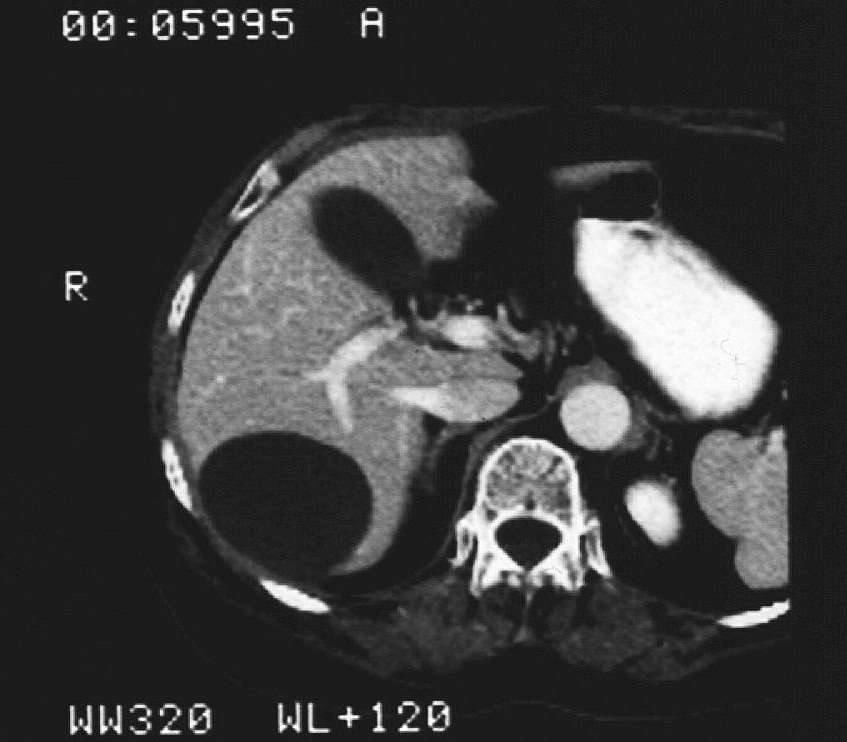

Compared to the surgical methods of past, nowadays these cystic lesions can be successfully treated percutaneously with alcoholic cyst sclerotization. (Figures 26., 27.).

Image

Figure 26. – Percutaneous ethanol cyst sclerotization ( filling up of the cyst before the sclerotization)

Figure 27. – US and CT examinations before percutaneous ethanol sclerotization (A: US examination, B: CT examination)

The puncture of the cyst is usually guided with US (rarely with CT). The puncturing needs to take place from the parenchymal side of the cyst. When its contents are removed the empty cavity is filled up with diluted contrast material to ensure that there is no contrast leakage to the surroundings. The 96% ethanol is only injected after the contrast material has been removed and no leakage was found. (The volume of the alcohol should not exceed 50-60% of the cyst or 100 ml.)

The injected ethanol is left in the cyst for 20 minutes. Following this, the alcohol is drained as well. Cystic regression is then regularly controlled with US or CT examinations. (Figures 28., 29.) Patient complaints usually cease within 4-6 weeks after the treatment.

Figure 28. – Control CT examination after percutaneous ethanol liver cyst sclerotization (9 months later) – significant regression